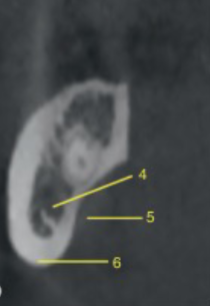

submandibular fossa

identify 5